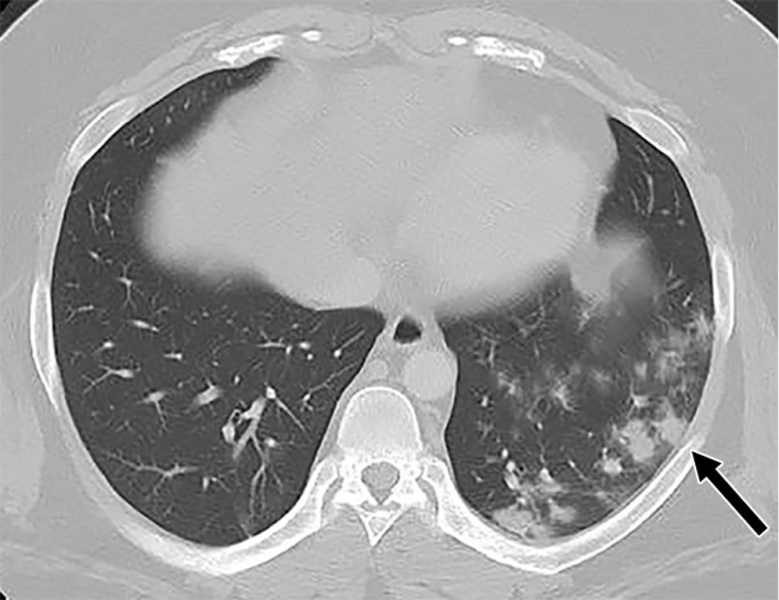

This photo gallery shows the variety of radiological presentations of COVID-19 (SARS-CoV-2) in medical imaging, including computed tomography (CT), radiograph X-rays, ultrasound, echocardiograms and magnetic resonance imaging (MRI). The radiology images show examples of typical COVID pneumonia in the lungs and the numerous complications the virus causes in the body in multiple organs, including the brain, kidneys, heart, abdomen and vascular system.